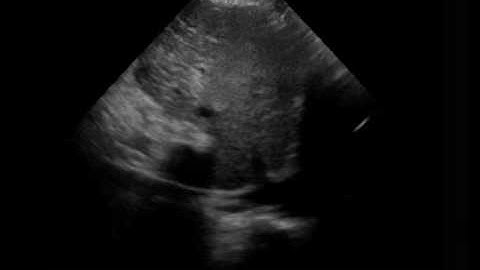

IVC plethora, dilated non collapsing IVC Echo #shorts